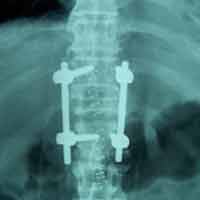

Post-op Ap

60 years old female with one& half months old fracture L1 presented with complete paraplegia with bladder & bowel involvement. She was treated with posterior decompression (Laminectomy), reduction of retroplused fragrant & pedicure screw fixation. Full neurological recovery on 6th day.

Case:1 Traumatic Fracture L1 with Cauda Equina